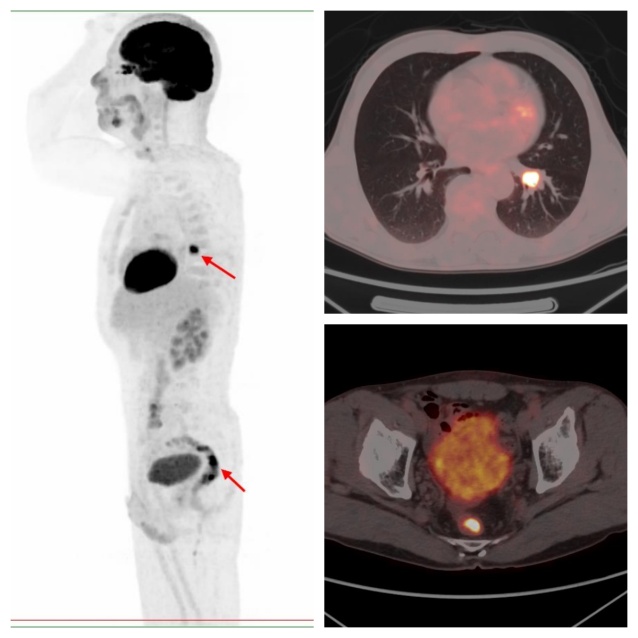

病例2,PET/CT示左肺下葉、直腸代謝異常,符合雙原發(fā)癌;之后患者行支氣管鏡下活檢,病理證實原發(fā)肺鱗癌;行腸鏡下活檢,病理證實為原發(fā)直腸潰瘍型腺癌。